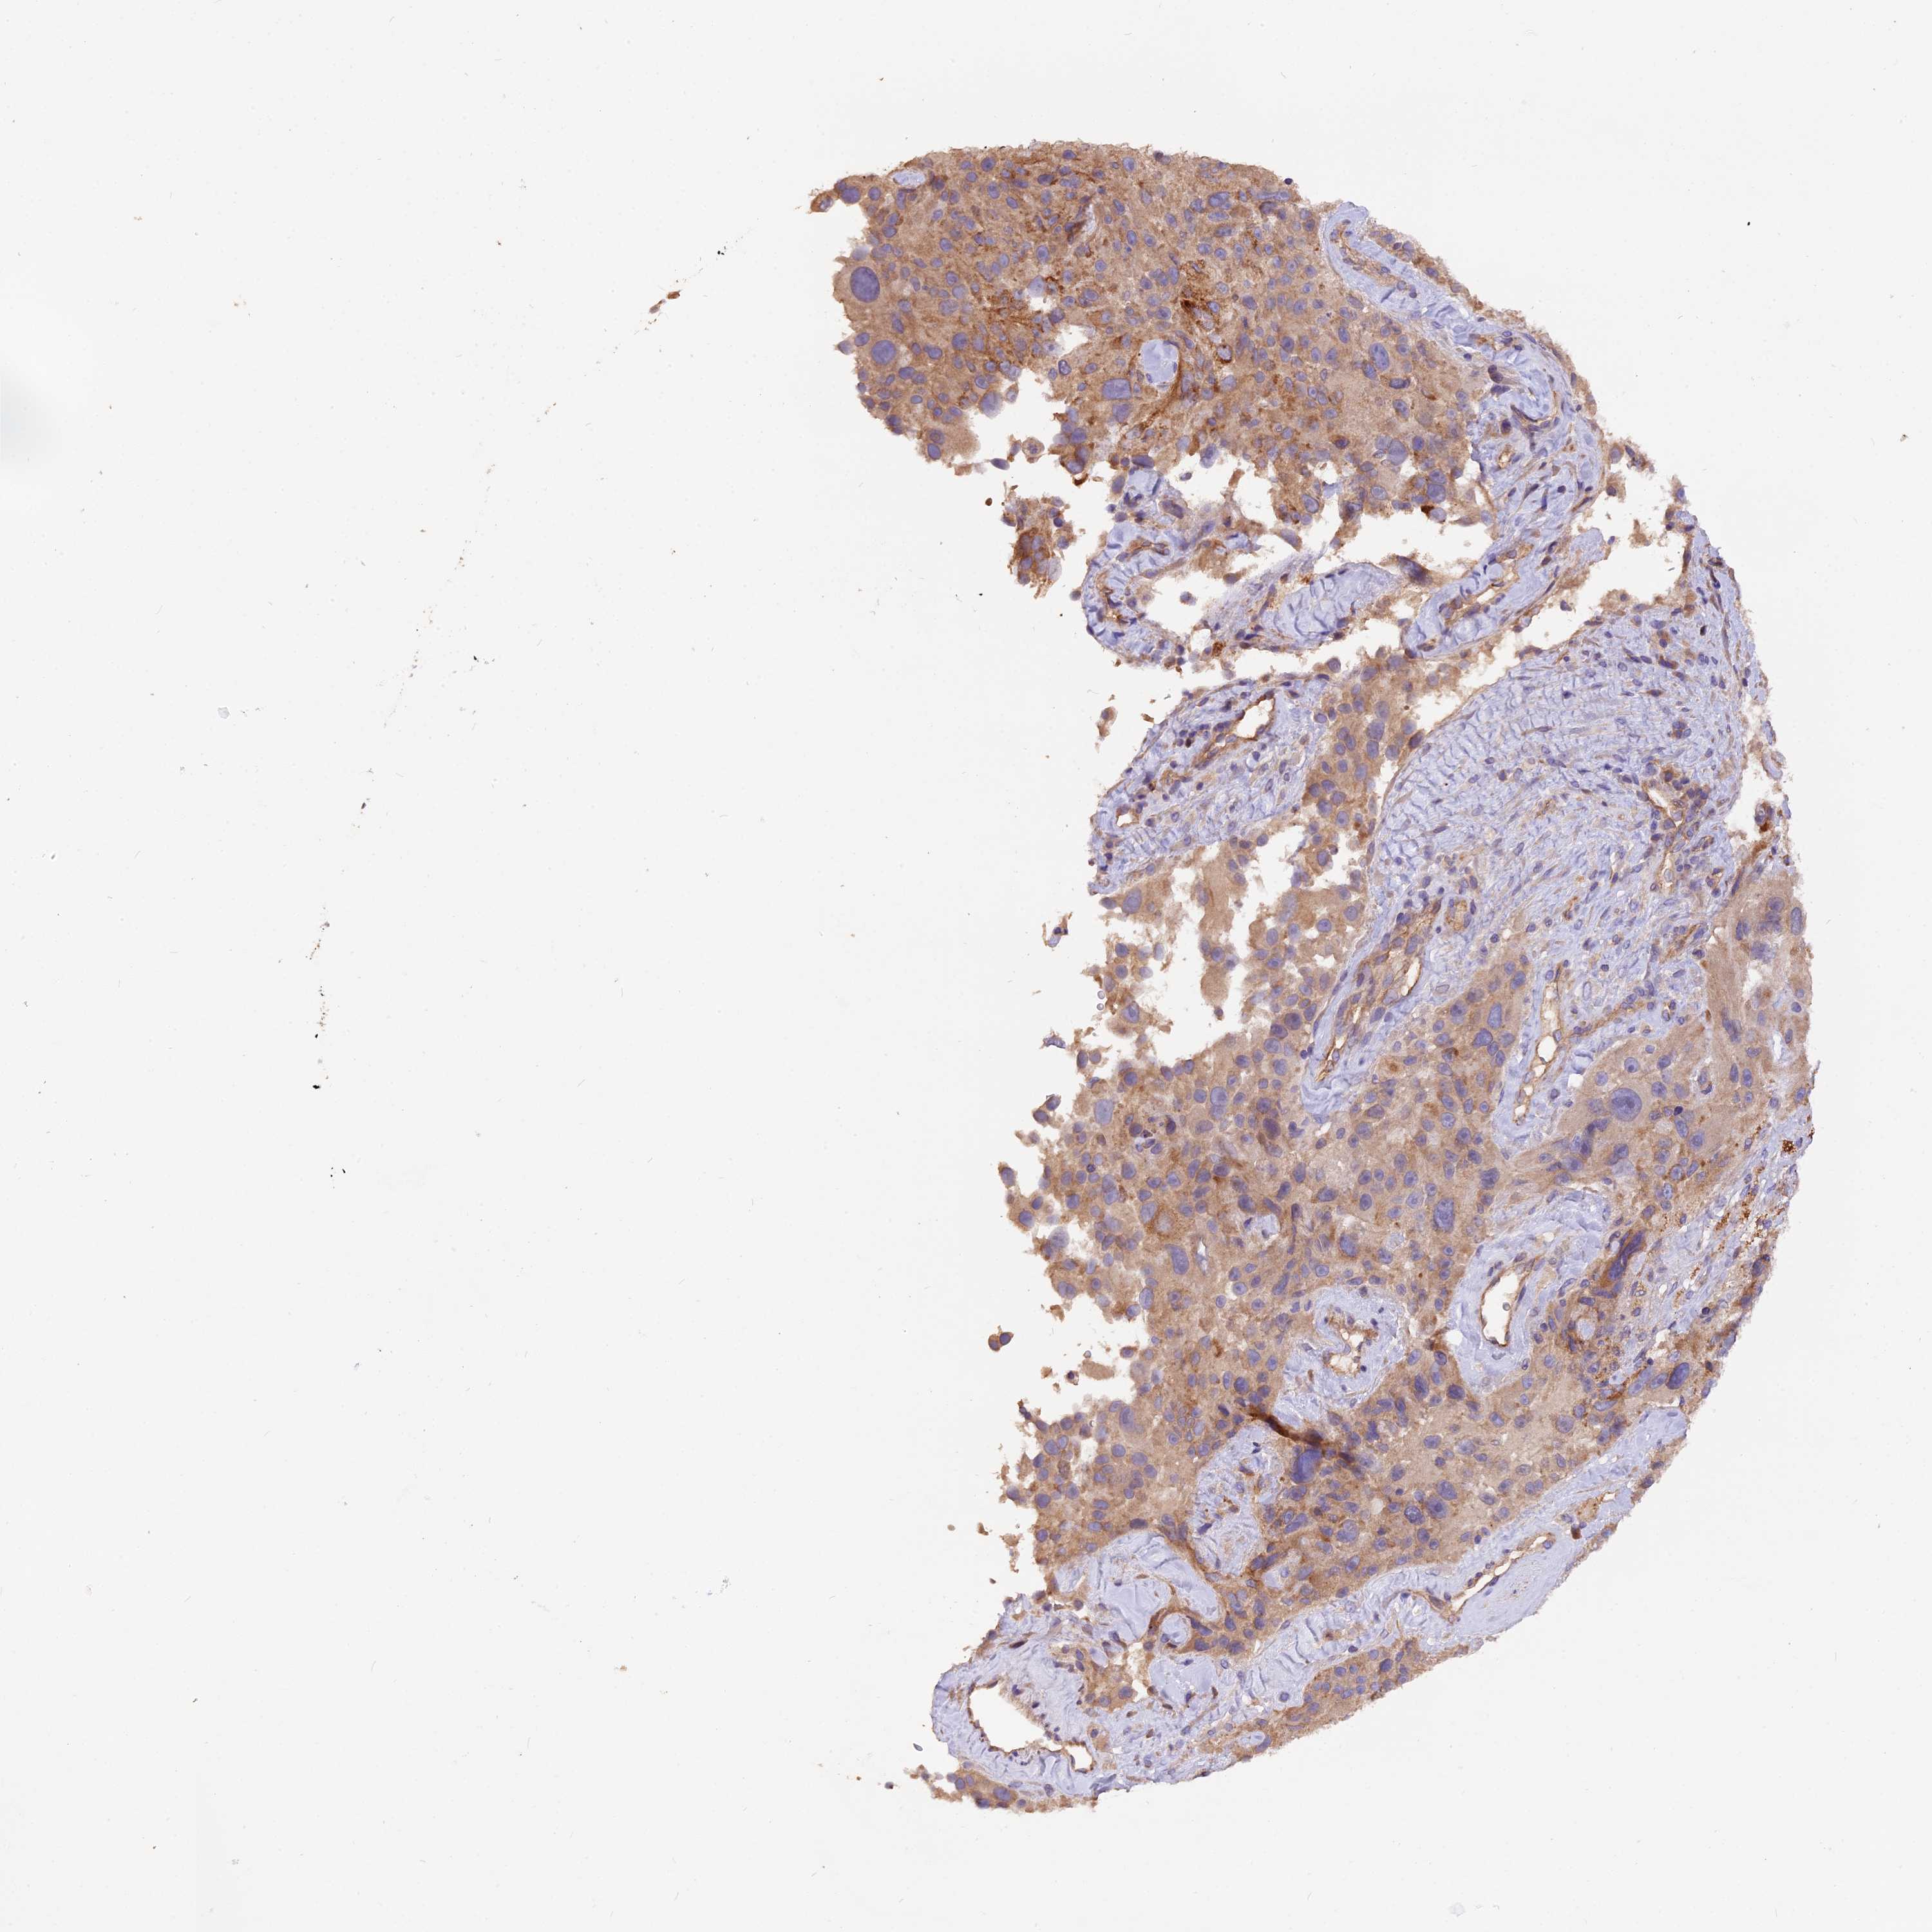

MELANOMA - Protein expressioni

A mouse-over function shows sample information and annotation data. Click on an image to view it in a full screen mode. Samples can be filtered based on level of antibody staining by selecting one or several of the following categories: high, medium, low and not detected. The assay and annotation is described here.

Note that samples used for immunohistochemistry by the Human Protein Atlas do not correspond to samples in the TCGA dataset.

Antibody stainingi

Antibody staining in the annotated cell types in the current human tissue is reported as not detected, low, medium, or high, based on conventional immunohistochemistry profiling in selected tissues. This score is based on the combination of the staining intensity and fraction of stained cells.

Each image is clickable and will lead to virtual microscopy that enables deeper exploration of all samples and also displays staining intensity scores, fraction scores and subcellular localization as well as patient and tissue information for each sample.

Antibody HPA041741

Staining

High

Medium

Low

Not detected

Intensity

Strong

Moderate

Weak

Negative

Quantity

>75%

75%-25%

<25%

None

Location

Nuclear

Cytoplasmic/membranous

Cytoplasmic/membranous,nuclear

Malignant melanoma, NOS

Malignant melanoma, Metastatic site